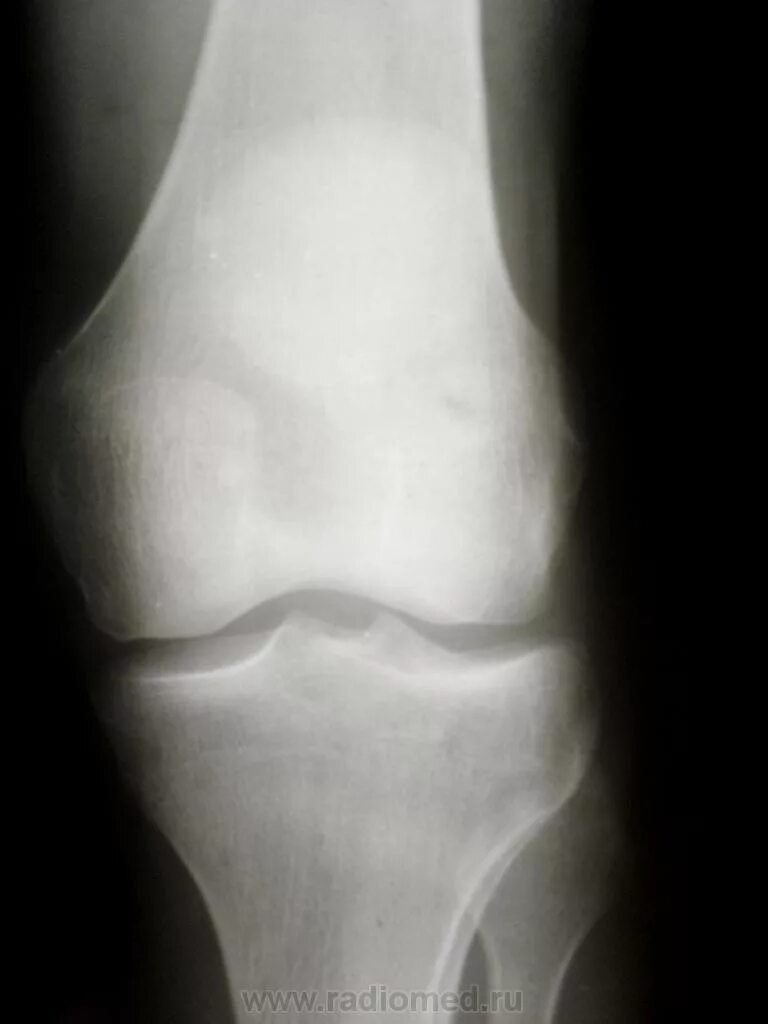

Лигаментоз коленного сустава рентген. лигаментоз тазобедренного сустава рентген. обызвествление в мягких тканях коленного сустава рентген. тендиноз тазобедренного сустава рентген.

Лигаментоз коленного сустава рентген. хондроматоз голеностопного сустава. лигаментоз надколенника. лигаментоз надколенника рентген.

Лигаментоз коленного сустава рентген. лигаментоз надколенника рентген. рентген коленного сустава пкс. повреждение связок коленного сустава рентген.

Лигаментоз коленного сустава рентген. оссифицирующий лигаментоз коленного сустава. лигаментоз связок коленного сустава. лигаментоз надколенника рентген.

Лигаментоз коленного сустава рентген. тендиноз коленного сустава рентген. пороз коленного сустава рентген. лигаментоз коленного сустава рентгенологическая картина.

Обызвествления в коленном суставе на рентгене. обызвествление мениска коленного сустава рентген. обызвествление связок коленного сустава на рентгене. менископатия коленного сустава рентген.